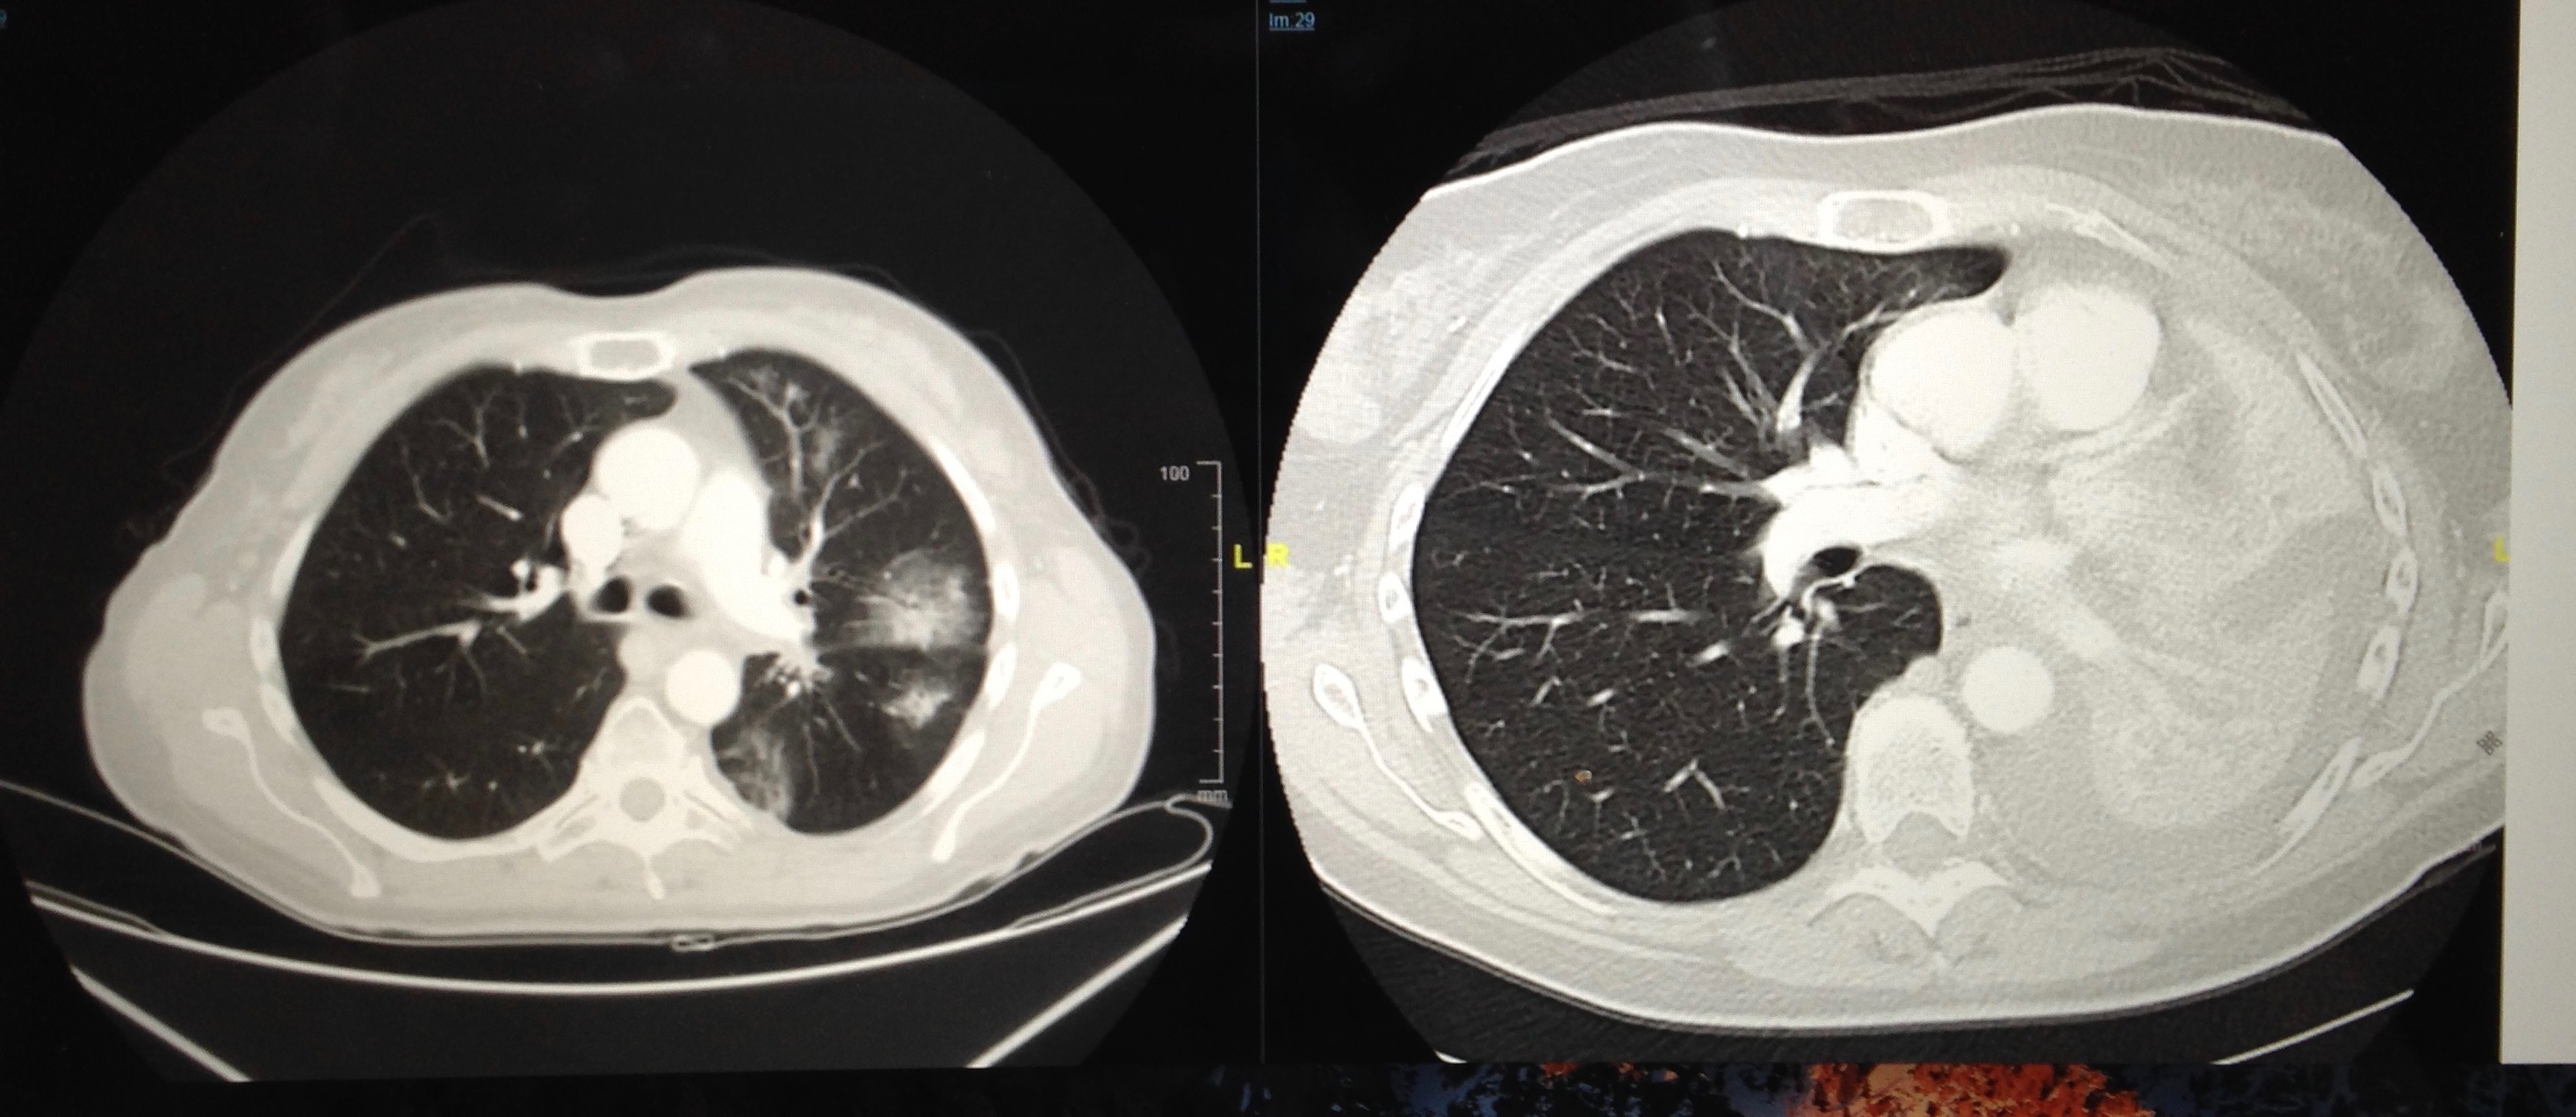

Since that first x-ray that showed a mass in my left lung hilum (contains major bronchi, pulmonary vessels, and lymph nodes), I’ve had one bronchoscopy, one PET scan, one liver biopsy, one spinal tap (when the cancer found my CNS), one heart CT (to see what the radiation and high cholesterol has done), one radiation mapping session (resulting in 4 tattoos!), 15 rounds of radiation (during which we stayed at the Hope Lodge in Worcester, MA), 22 ECGs (done during the lorlatinib clinical trial), at least 47 blood draws, 47 CT scans (chest, abdomen, pelvis all at the same time), 40 brain MRIs, and approximately 60 oncology appointments (went frequently at the start of the trial, several with radiation oncologist). That’s a lot of trips from Blue Hill to Boston. Dan has been my constant companion; driving, waiting patiently outside testing rooms (or in the car during COVID), and being there for my appointments. Other family members have joined us, or helped to care for things at home.

I started crizotinib as my first treatment. After 16 months, when the cancer found my brain meninges, I began lorlatinib. It reduced the cancer by 80% quickly, and I remain stable on it today. The drugs have some nasty side effects (but the alternative isn’t really one is it?) and there are other medications, ways of eating, and self care that help. As I say when asked, “I’m doing well, all things considered!”